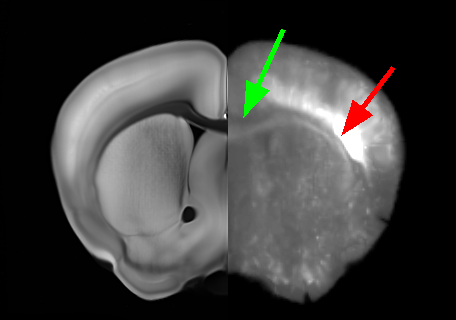

For registration, each CLARITY volume I0subscript𝐼0I_{0} was downloaded from the NeuroData cluster. They were resampled to a 50 μm𝜇𝑚\mu m resolution and registered to ARA atlas image J1subscript𝐽1J_{1} with 12-parameter affine alignment under MI matching. Deformable registration was then done with MI-LDDMM as implemented in ndreg. A cascaded-α𝛼\alpha approach was adopted in which a smoother registration with α=0.05𝛼0.05\alpha=0.05 was followed by registrations at α=0.02𝛼0.02\alpha=0.02 and α=0.01𝛼0.01\alpha=0.01 to refine the results (Fig. 2). Both ARA-aligned CLARITY volumes and CLARITY-aligned ARA annotations were uploaded to the NeuroData cluster. This allowed us to visualize ARA annotations overlaid on the terabyte-scale CLARITY images (Fig 1). Deformable registration was done with SSD-LDDMM and Mask-LDDMM to demonstrate the advantages of MI-LDDMM. For validation MI-LDDMM was also compared to SyN ANTs [1] with MI cost and σ=1.0𝜎1.0\sigma=1.0 mm Gaussian regularization (Fig. 3).

Refer to caption

(a) SSD- LDDMM

(b) Mask- LDDMM

(c) MI- LDDMM

(d) SyN

Figure 3: Comparison of SSD-LDDMM (3(a)), Mask-LDDMM (3(b)), MI-LDDMM (3(c)) and SyN ANTs (3(d)) registration of CLARITY volume. Panes (3(a)-3(d)) have an ARA coronal slice on the left juxtaposed to the corresponding aligned CLARITY slice on the right. Green arrows point out that the corpus callosum is misaligned by SSD-LDDMM but aligned correctly by MI matching. Red arrows show that SSD-LDDMM distorts bright regions. Fiducial landmarks were manually placed in the corpus callosum, and midbrain of the acquired volumes. Pane (3(e)) compares mean errors between the deformed CLARITY and ARA landmarks after registration.